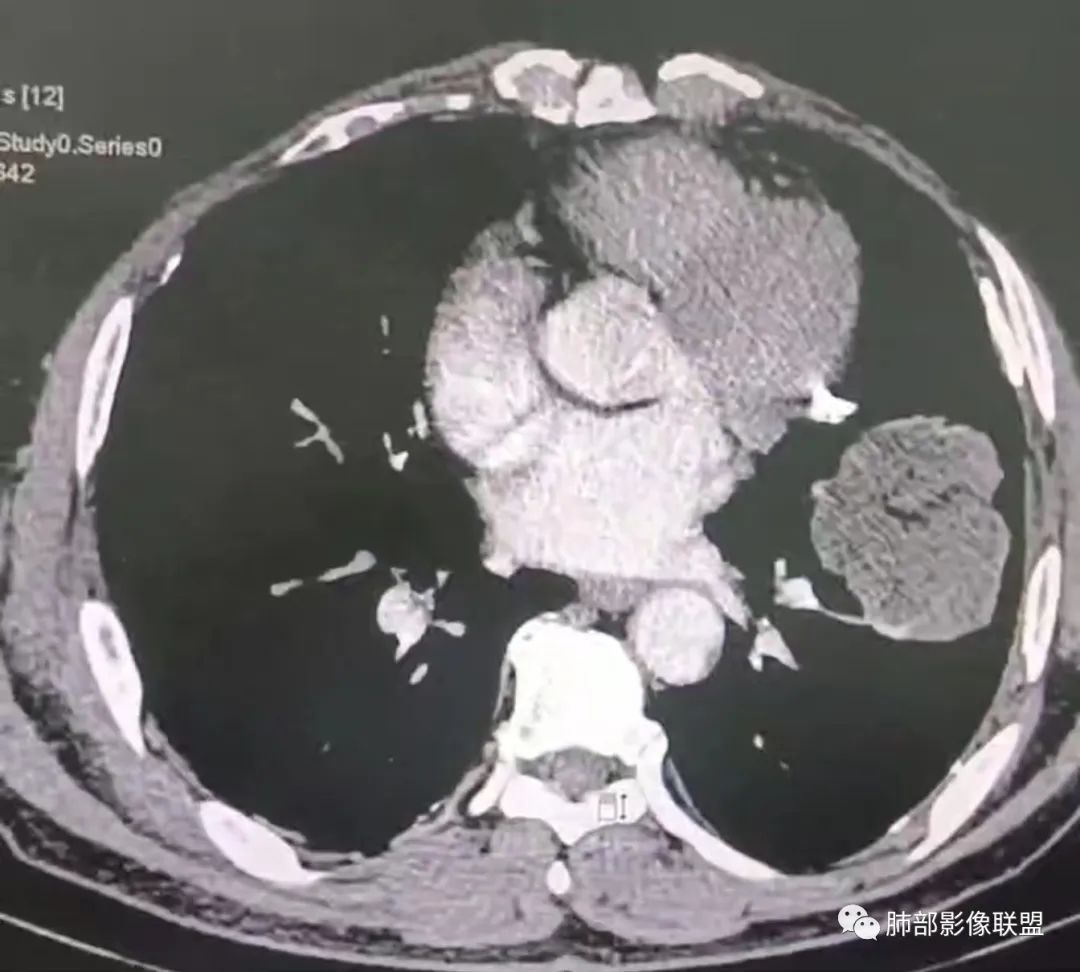

左肺上叶大肿块,膨胀性生长,边界清,密度较低,见部分坏死区,强化弱,肿块见支气管充气V扩张征,分布僵直,枯树枝特点,另一个重要特点血管造影征,淋巴瘤,肿块长轴与胸膜平行,与隐球菌鉴别,隐球荚膜抗原检查,明确诊断经皮肺穿刺。另胸膜钙化(问诊既往有无患胸膜炎病史)。

左肺上叶胸膜下肿块,宽基底与胸膜相连,跨叶裂,边缘清晰膨隆,其内支气管充气,部分扩张、僵直,无明显强化,血管造影征,考虑淋巴瘤,鉴别腺癌

左肺胸膜下巨大占位,跨叶裂,宽基底与胸膜相连,胸膜钙化,平扫密度较低,强化不明显,可见内部血管显影,支气管充气征和扩张,考虑为恶性,倾向于淋巴瘤

我要修正一下观点了:仔细看了视频,肿块占位效应明显,对周围血管,支气管有推挤,增强后强化不明显,NSE增高,半年体重下降25公斤,虽然有内部支气管扩张,血管漂浮,边界清楚支持淋巴瘤,但强化太低,膨隆,占位推挤太明显(淋巴瘤一般没有这么明显的占位效应),胸膜关系有载桩,恶病质明显(乏力,半年体重下降了25公斤),NSE也明显增高,就不支持淋巴瘤了。还是考虑外朝内的恶性肿瘤,间质来源的肉瘤伴有神经内分泌分化或者大神泌。

不支持淋巴瘤的有四点:1、对周围血管支气管推挤明显。2、胸膜有栽桩,3、强化太弱(淋巴瘤一般还是中度以上甚至高度强化多见),4、NSE升高明显,体重下降太明显。

大肿块,边缘光滑,深分叶

近端支气管堵塞、推移为主

部分类似于脐凹征

内部支气管扩张

肺动脉推移为主,边缘部分进入

大肿块、表面光滑但深分叶,肺门侧支气管堵塞

回头看,内部支气管近端其实不连续,伴随肺动脉不存在

这两点就不符合

4)密度:肿块平扫为软组织密度,由于体积较大,内部常见大片状坏死,可出现不规则厚壁空洞或坏死内多发无壁小空洞,坏死多不均匀:坏死灶内可见如柳絮样的斑片样强化灶,坏死边缘与非坏死区分界不清本例坏死较明显,密度不均匀。

5)肿瘤强化方式:肺部恶性肿瘤强化程度与其血供丰富程度相关,血供丰富多强化明显,反之则较差。由于PSC 周边实性部分富血供及内部黏液变性、坏死,增强后肿块多数呈轻-中度边缘环形强化或不均匀小斑片状强化。国外学者对照病理发现肿瘤细胞或胶原组织增强扫描时强化,无强化的低密度区代表了黏液样变性区和出血坏死区。